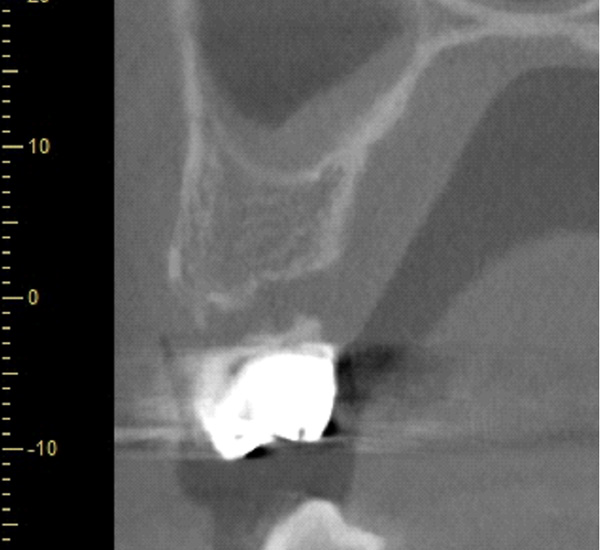

| 年代・性別 | 50代 男性 |

|---|---|

| 主訴 | 右下の歯がないのでインプラントをして欲しい |

| 治療期間 | 約6ヶ月 |

| 費用 | 600,000円 |

| 治療内容 | インプラント、骨造成、結合組織移植、セラミック修復 |

| 治療に伴うリスク | インプラント周囲炎 セラミックの破折、脱離 |

*キャンセルポリシーをご一読のうえご予約ください